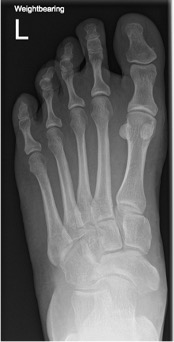

- Plain standing radiographs allow a dynamic assessment of deformity (Figure 14)

Figure 14: clear AVN of the body of the talus with arthrosis at all peri-talar joints